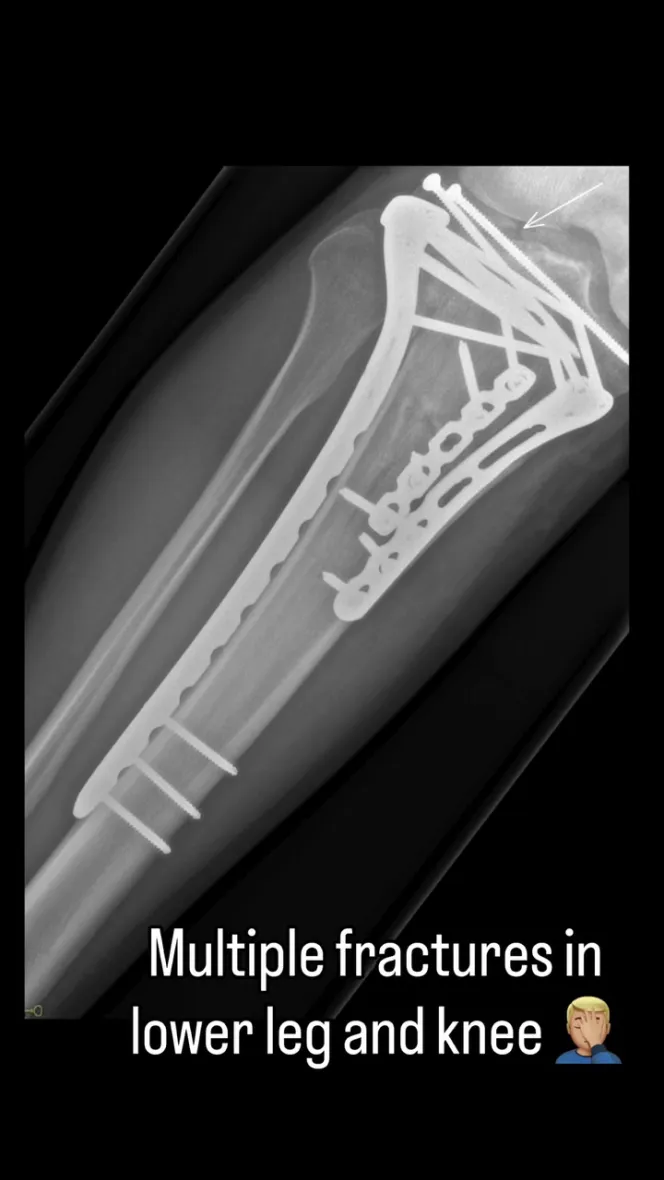

X-ray of Sir Chris Hoy's broken leg with multiple fractures.An x-ray of Hoy’s leg after the crash

He shared a video of his treatment, which showed the gruesome nature of his tibial plateau fracture injury. Hoy also disclosed that he has video footage of the accident itself but has been too traumatised to watch it.

He said: “I launched off this jump and overshot it and my leg and knee just exploded. There will always be some compromise in [the leg]. It’s been a tough few months but I feel like I’m out the worst of it now.